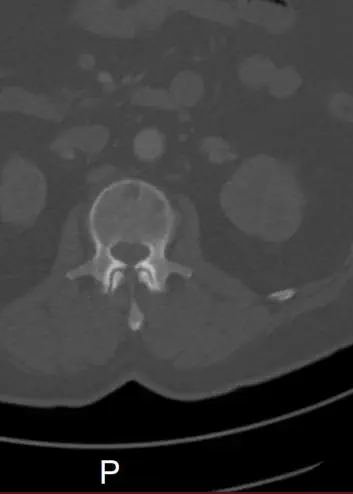

CT - Bilder der Punktion des Beckenkamm

Punktion

Punktion unter CT